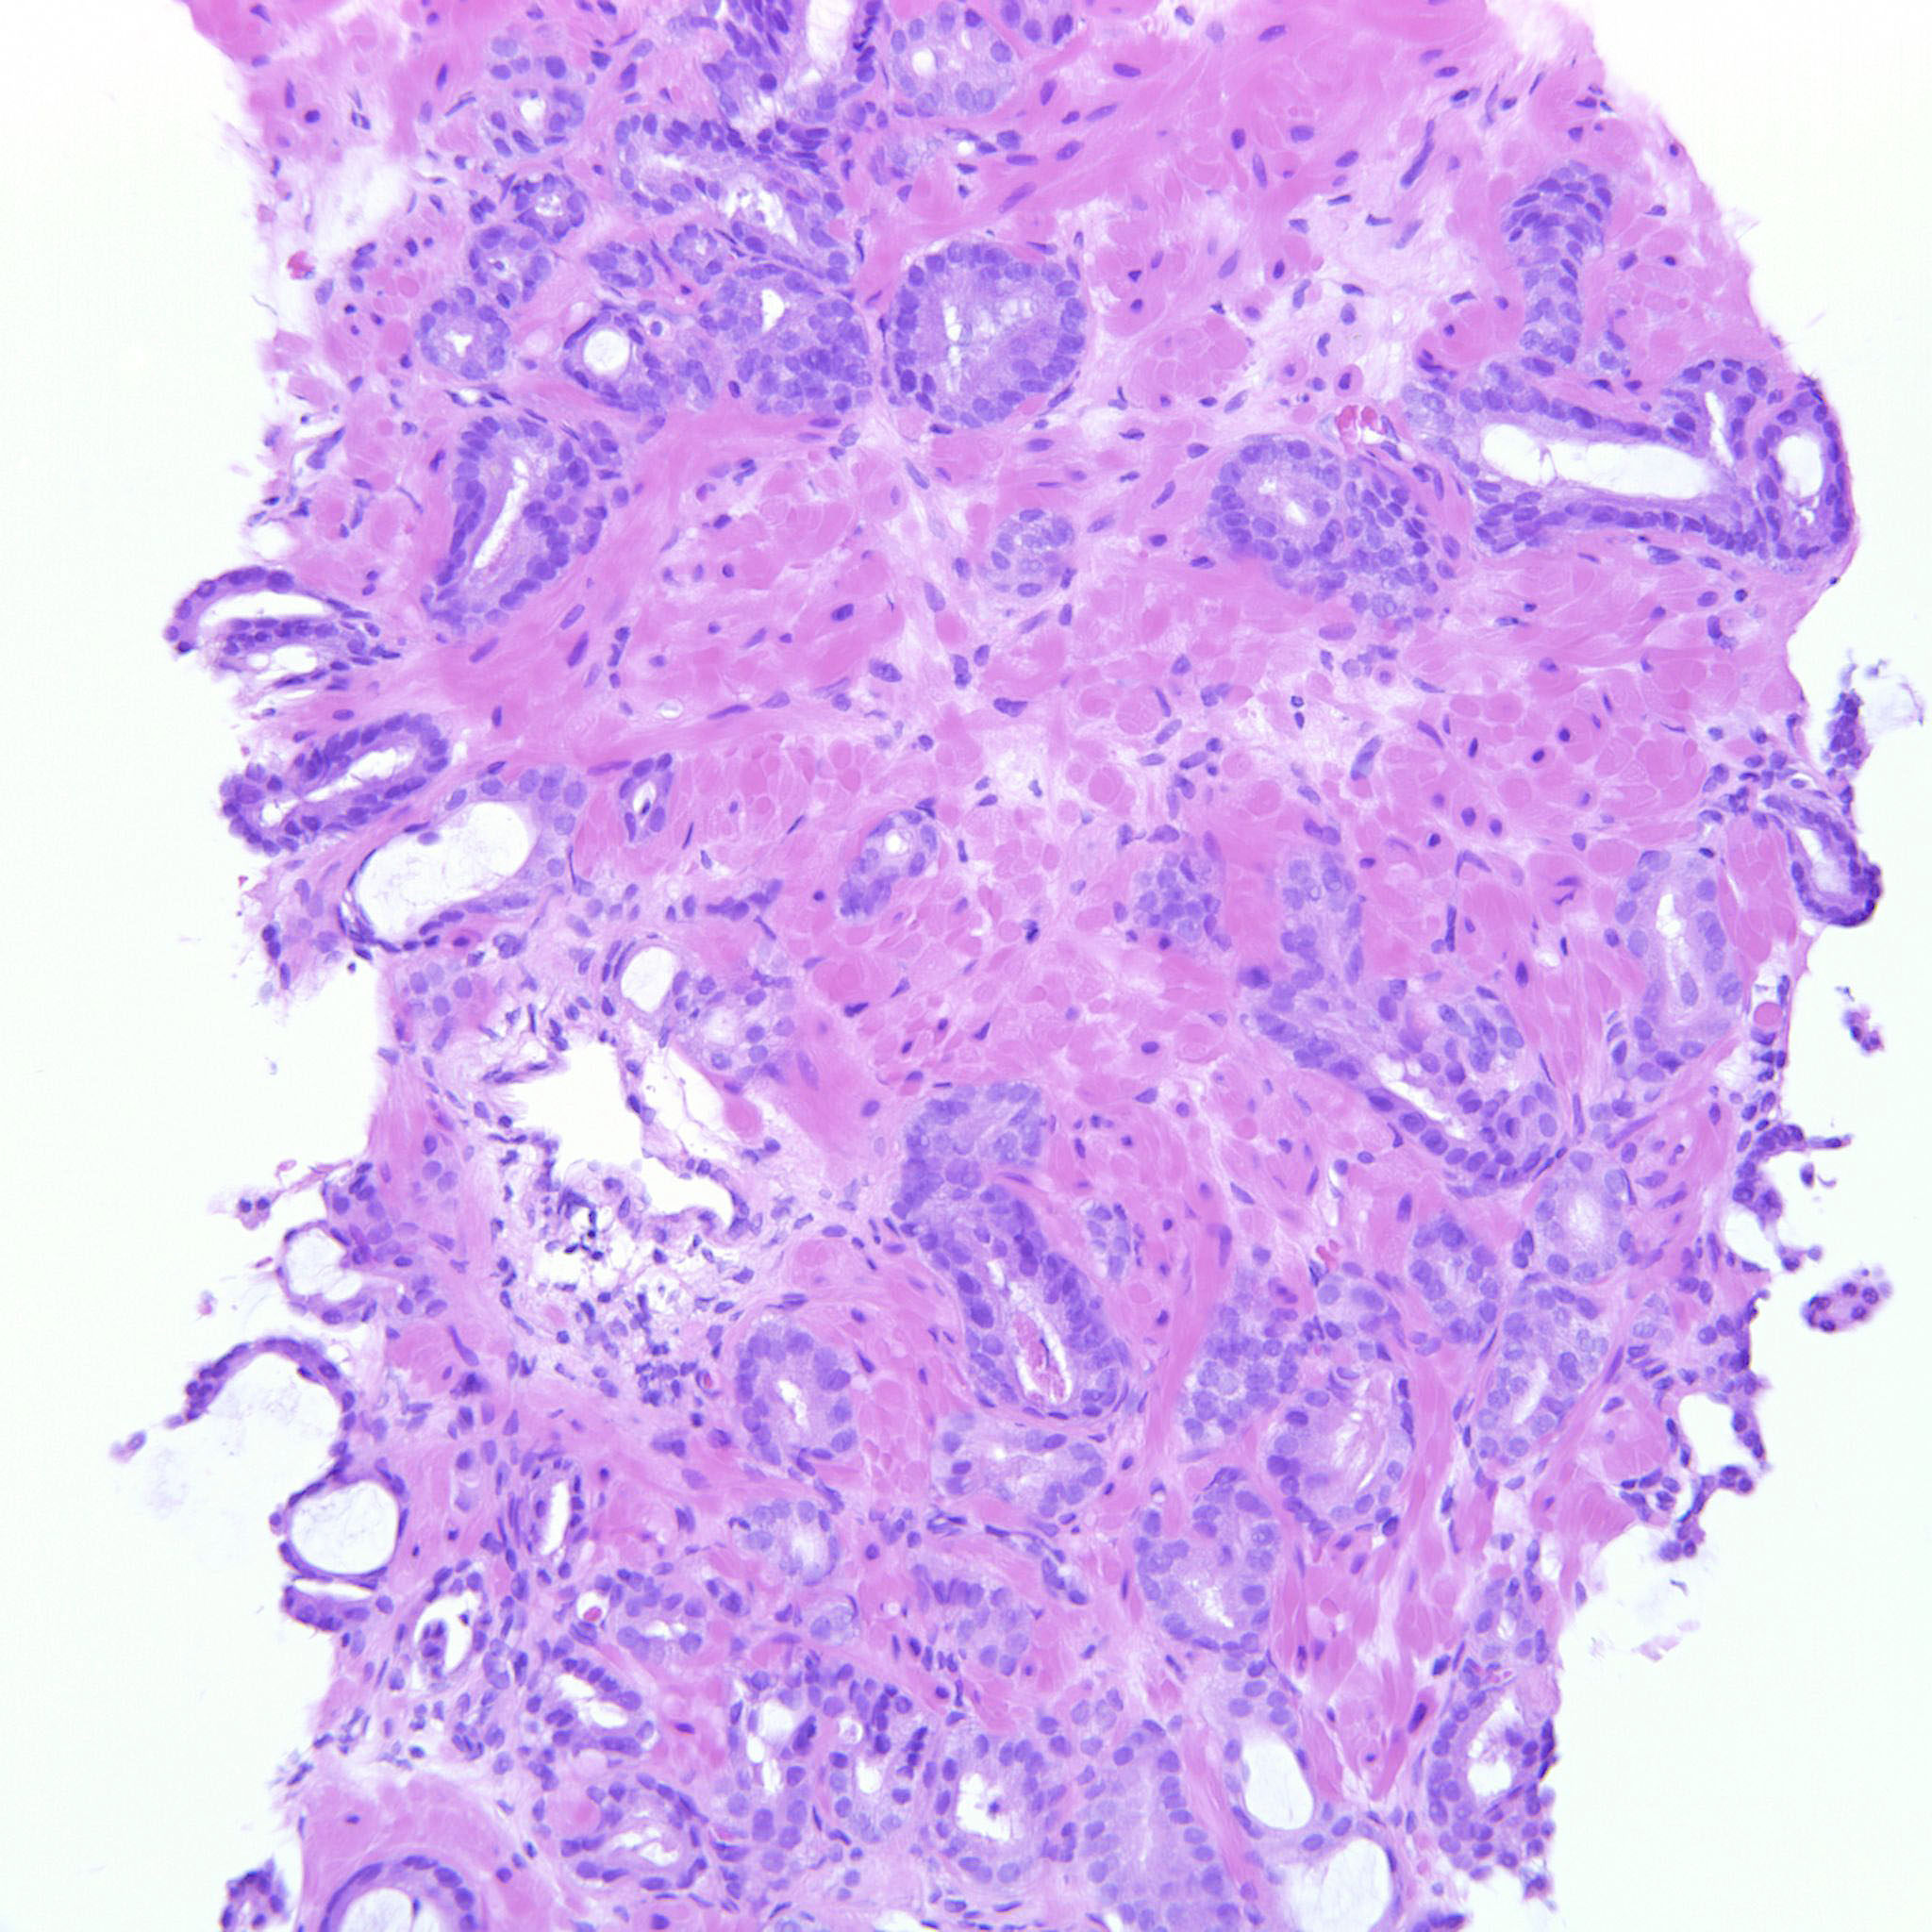

Consensus grade: GS 3+3=6 (ISUP 1)

Case description (by case creator):

3+3=6 bordering towards 3+4. There are rare seemingly poorly formed glands but they can still be overlooked.